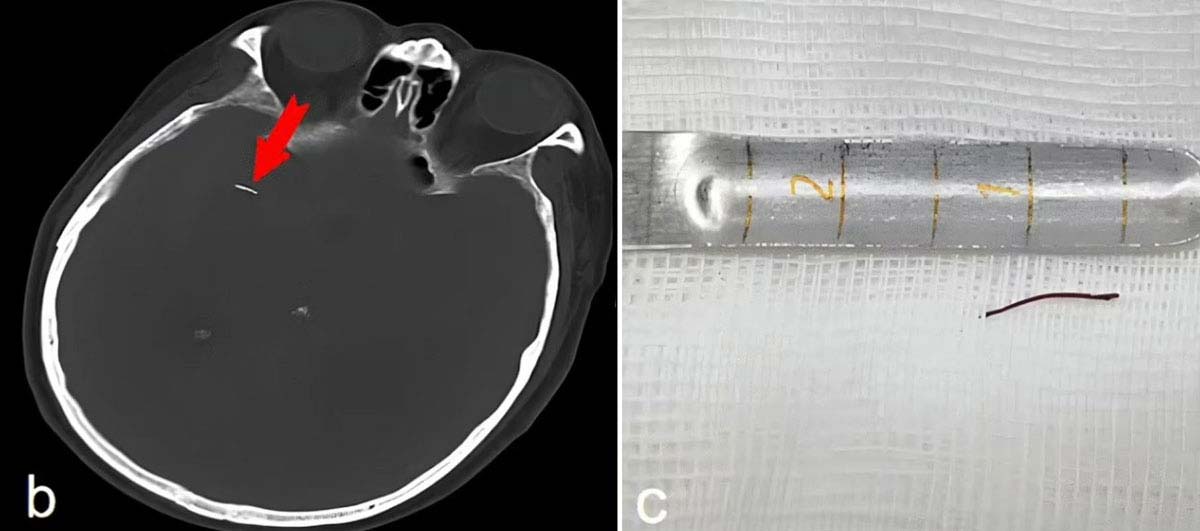

A씨 뇌를 CT(컴퓨터단층촬영)로 찍어 확인한 결과, 뇌동맥류가 아닌 뇌에 박혀있던 바늘 때문에 출혈이 일어난 것으로 나타났다. 오른쪽 눈 뒤 뇌를 통과하는 중대뇌동맥에 바늘이 꽂혀 있었다. 의료진은 A씨를 두개내 가성동맥류로 진단했다. 가성동맥류는 압력이 아닌 외상 등으로 동맥이 손상돼 생기는 합병증으로, 혈관이 누출됐으나 주변 조직에 의해 제자리에 고정된 상태를 말한다. 의료진은 바늘을 제거하기 위해 A씨 두개골 일부를 자른 후, 뇌경질막을 절단하고 수술용 현미경을 삽입해 바늘을 찾아 제거했다. 이후 혈관의 파열된 부분을 매우 작은 금속 클립으로 봉합했다. 제거한 바늘은 약 1.3cm(0.5인치)로 금색이었고, 약간 뾰족했다.